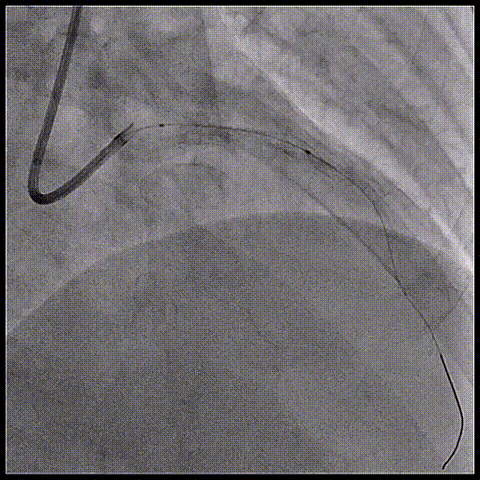

1、7F EBU3.5导管;IVUS导管;6F Telescope™导引延长导管;

2、SION导丝;

Telescope™导引延长导管支撑,IVUS导管顺利通过